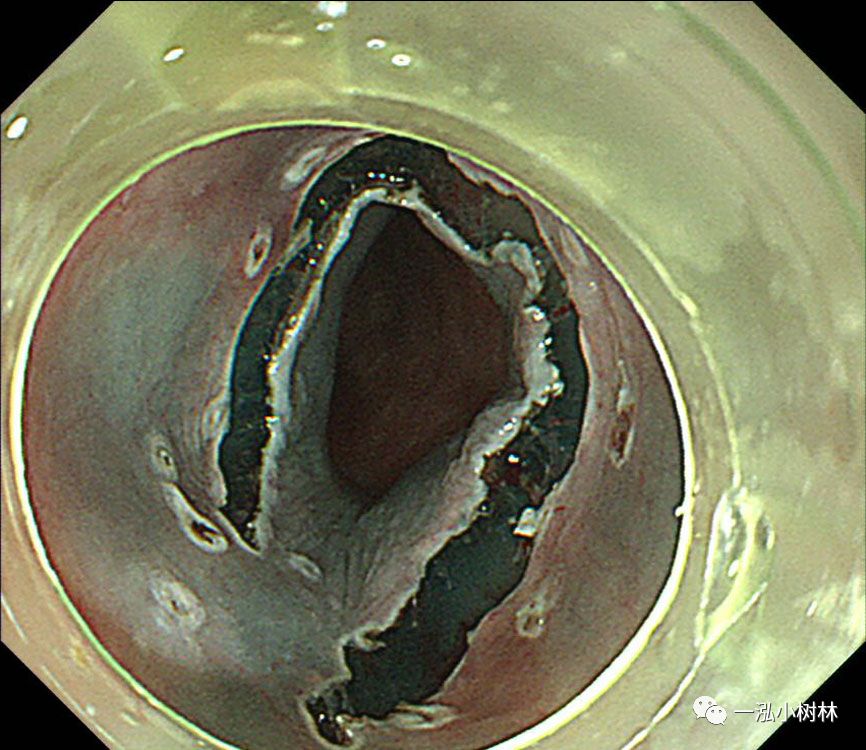

图7 使用IT刀进行纵向黏膜切口,并完成C形切口。